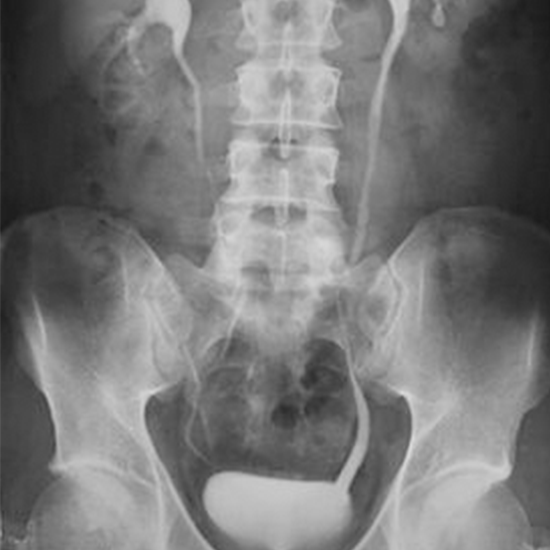

MRI (Magnetic Resonance Imaging )Pyelogram refers to imaging of the urinary collecting system. It produces detailed pictures of the renal pelvis and ureter using magnetic waves. It is also known as MRI pyelography or MRI urography. It is used to find problems related to the urinary tract such as blockage, narrowing due to kidney stones, cancer, or any obstruction.